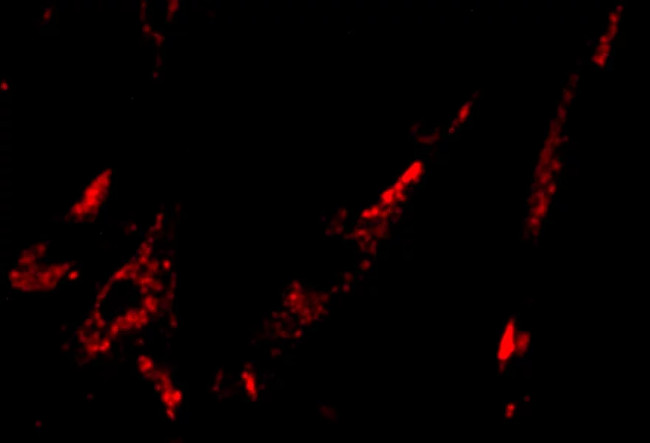

When injecting this beta-galactocidase compound into the body, under infrared light, other unrelated cells and tissues can emit green light, however, with cancer cells it will emit Red light indicates a dangerous level of cells to destroy.